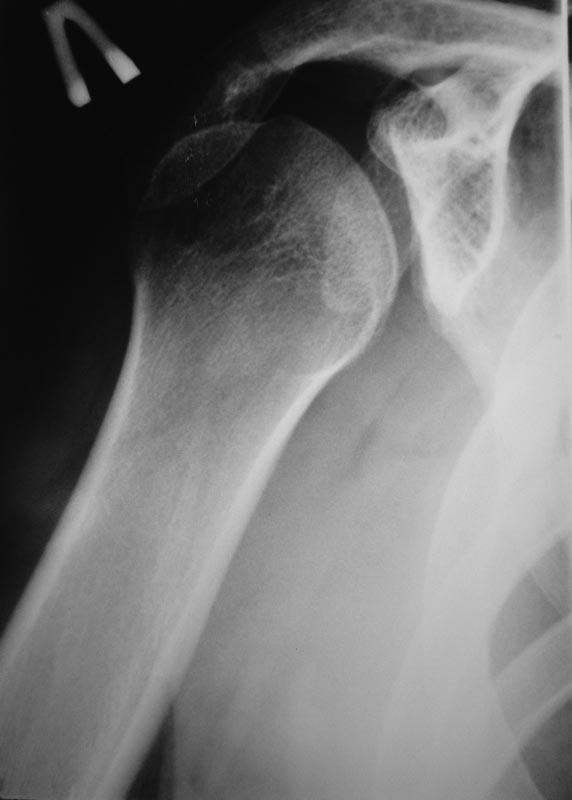

Уважаемые коллеги!Требуется ваша помощь. На консультацию обратился пациент 30 лет с жалобами на ограничение активных движений в левом плечевом суставе. Пассивные – в полном объеме. Со слов – имела место некая родовая травма. К тому же отмечается незначительный дефицит иннервации n.radialis (снижение «силы» разгибателей-сгибателей в кистевом суставе и отведения 1 пальца; неврологи никакого специфичного лечения не назначают). Также имеется контрактура локтевого сустава: сгибание в полном объеме, разгибание 150 градусов, супинация в пределах 7 градусов. Функция конечности в принципе устраивает. Скелетных травм в анамнезе нет. Вопрос: есть ли смысл заниматься какими-либо реконструкциям на плечевом суставе и как можно улучшить функцию скомпрометированных суставов? Заранее всем благодарен

Уважаемый Михаил, у Вашего пациента вероятнее всего "родовая травма" была скелетной, т.е. во время родовспоможения произошел эпифизеолиз дистального эпифиза плечевой кости. Клинически это проявляется некоторым непродолжительным ограничением подвижности в конечности, консолидация (учитывая возраст) проходит достаточно быстро (7-10 дней). Бывает, что при выписке из роддома ребенка уже ничего не беспокоит. Имеющийся на снимке локтевого сустава варус дистального метафиза плеч кости может быть результатом такой травмы. Что касается неврологии, при подобной травме может произойти повреждение лучевого нерва, но это как правило следствие больших смещений эпифиза (заметили бы сразу). Второй вариант - роды столь травматичны, что повредили и плечевое сплетение - проксимальный паралич Эрба, который либо не распознали, либо плохо лечили, в итоге ограничение амплитуды подвижности в плечевом суставе.